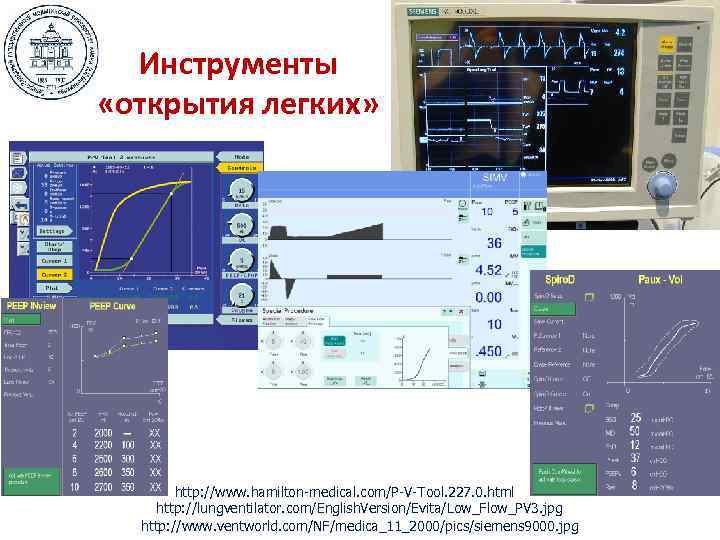

Инструменты «открытия легких» http: //www. hamilton-medical. com/P-V-Tool. 227. 0. html http: //lungventilator. com/English. Version/Evita/Low_Flow_PV 3. jpg http: //www. ventworld. com/NF/medica_11_2000/pics/siemens 9000. jpg

Инструменты «открытия легких» http: //www. hamilton-medical. com/P-V-Tool. 227. 0. html http: //lungventilator. com/English. Version/Evita/Low_Flow_PV 3. jpg http: //www. ventworld. com/NF/medica_11_2000/pics/siemens 9000. jpg